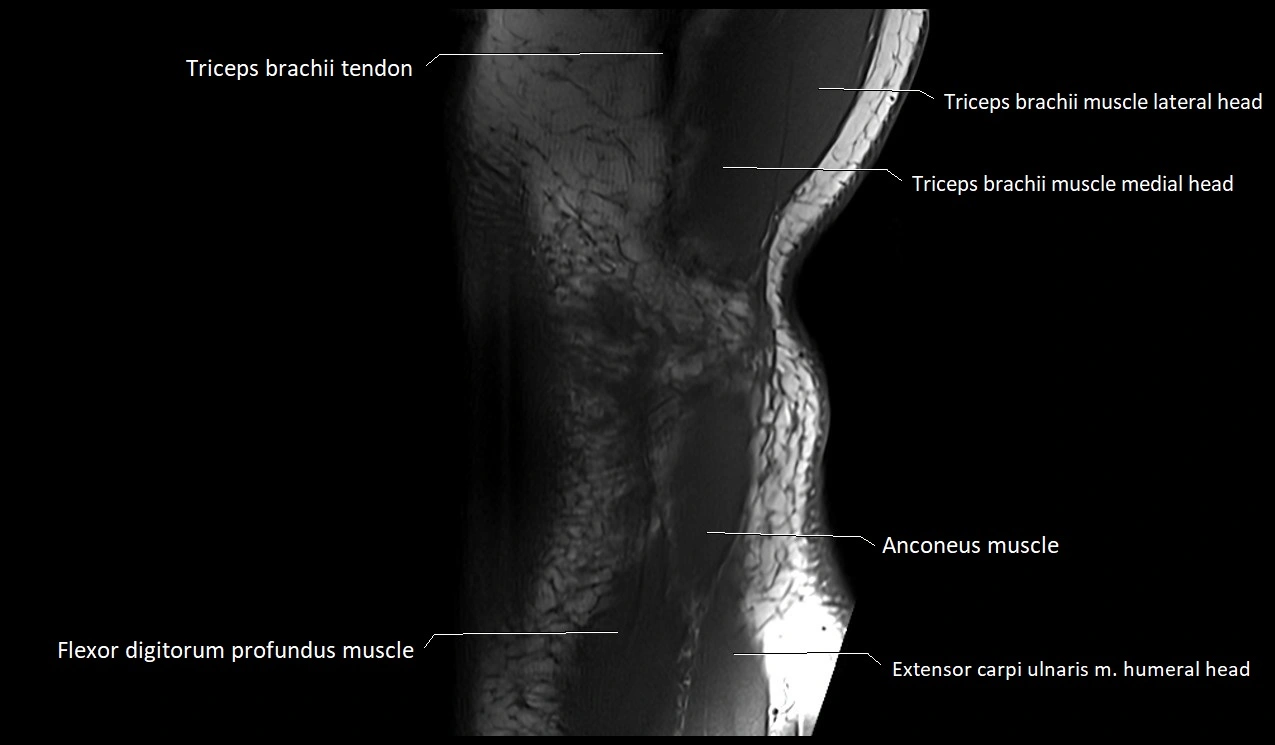

MRI image

image